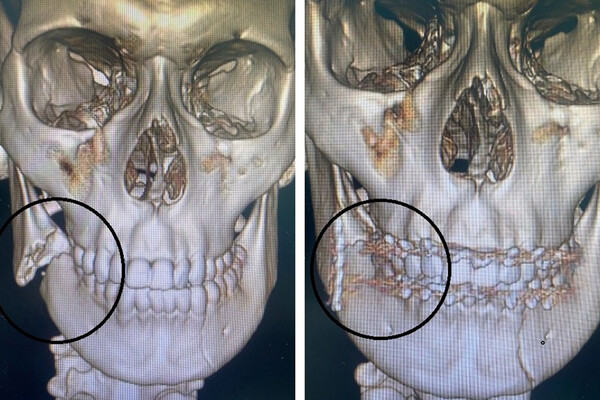

«После осмотра и диагностики был поставлен диагноз — открытый двусторонний перелом нижней челюсти. Мальчика госпитализировали в отделение оториноларингологии и челюстно-лицевой хирургии для проведения хирургического лечения», — рассказал челюстно-лицевой хирург больницы Владислав Слепов.

Доктор отметил, что сначала подростку наложили шины на верхнюю и нижнюю челюсти, а затем во время операции скрепили нижнюю челюсть титановой пластиной. Юноше предстоит долгое время питаться через трубочку — как пояснил медик, для полного срастания отломков необходимо полностью обездвижить челюсть.